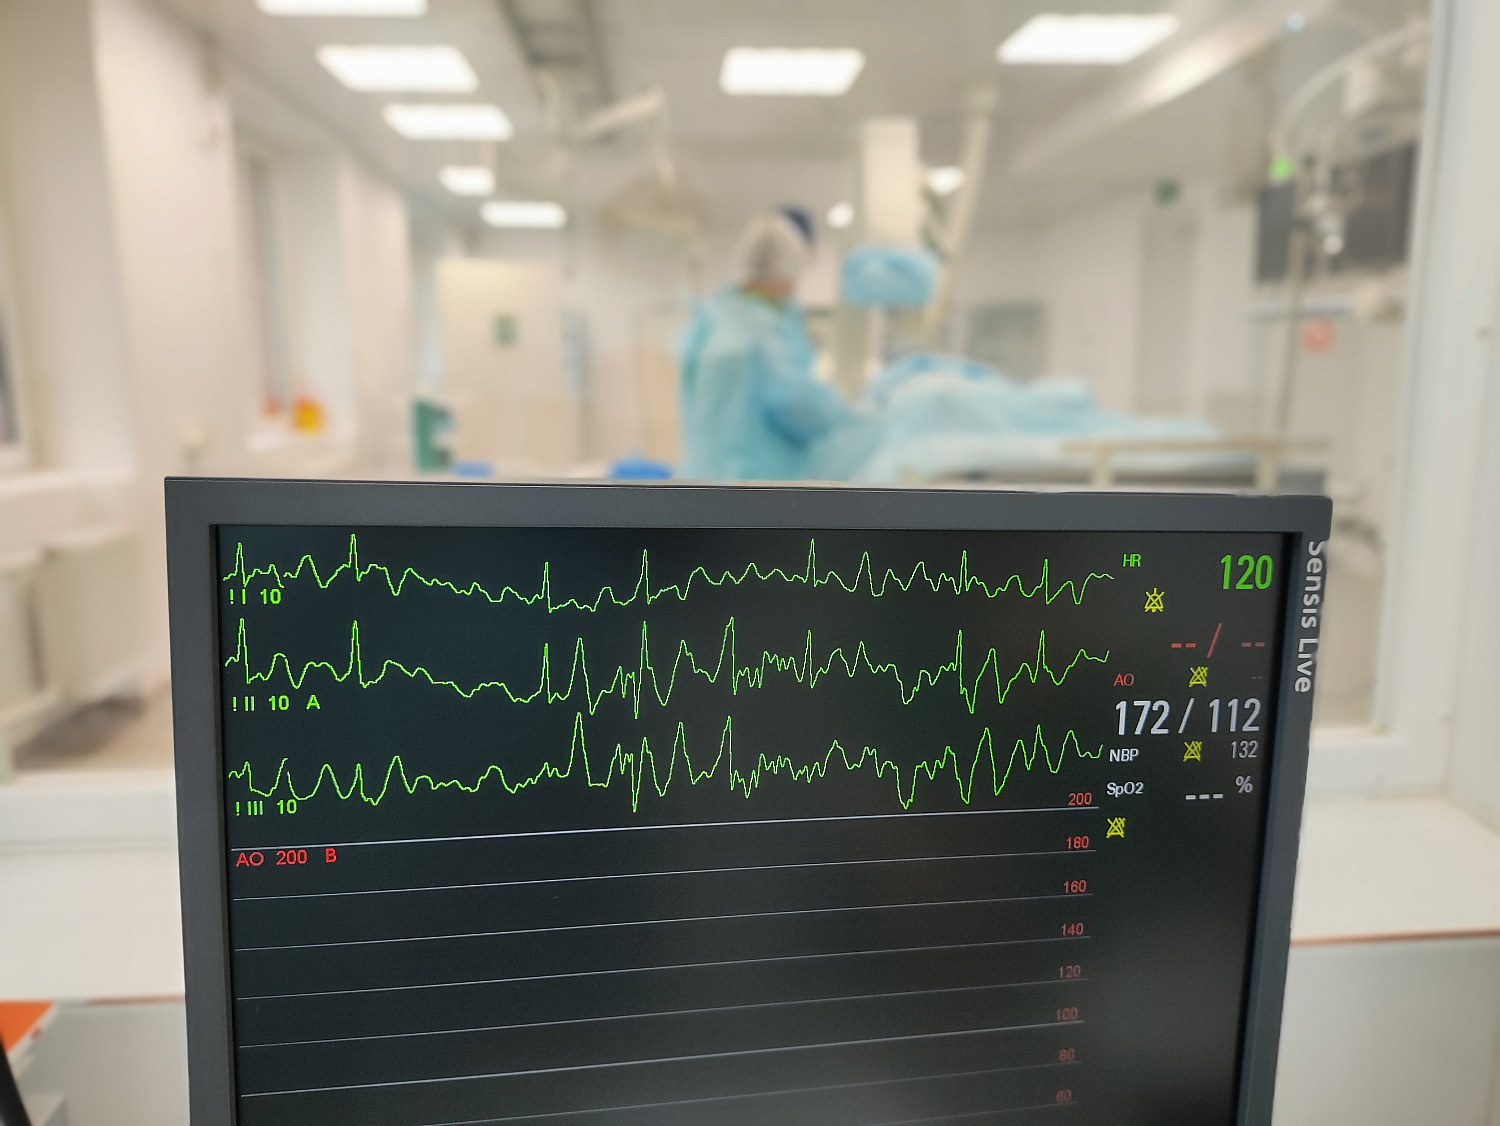

Первую коронарографию пациентке с ишемической болезнью сердца 4 сентября выполнил врач по рентгенэндоваскулярным диагностике и лечению отделения РХМДЛ, к.м.н. Евгений Андреевич Глухов.

«В ходе ангиографического исследования с помощью катетера в сосуд вводят йодосодержащее рентгеноконтрастное вещество, которое не пропускает рентгеновские лучи и, смешиваясь с кровью, делает просвет сосуда видимым под рентгеном, - рассказал Евгений Андреевич. - Например, при ишемической болезни сердца исследованию подвергаются коронарные сосуды, поэтому данную разновидность исследования называют коронарографией. При необходимости ее сочетают с эндоваскулярными или внутрисосудистыми видами хирургических вмешательств – стентированием, ангиопластикой».

Ежегодно в ОККД проводится более 2,5 тыс. эндоваскулярных вмешательств при ишемической болезни сердца, более 6 тыс. диагностических исследований и порядка 1,5 тыс. операций при различных формах нарушения ритма. Данный ангиографический комплекс стал четвертым по счету в арсенале врачей кардиодиспансера.